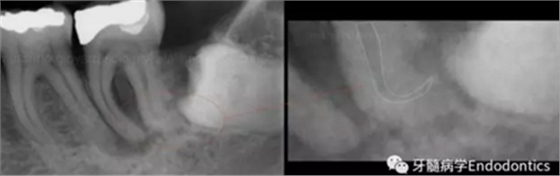

圖1.探查冠方2/3可以獲得有關(guān)根管系統(tǒng)解剖形態(tài)的相關(guān)信息,獲得根管彎曲和多重彎曲程度,或者是否存在根管彎曲的一些重要反饋。醫(yī)生需要重視五種可能遇到的根管解剖類型(包括融合、彎曲、多重彎曲、分歧、分支)。

當(dāng)建立直線通路、找到所有的根管口后,重心應(yīng)轉(zhuǎn)移到根管預(yù)備上。若牙髓存在活力且持續(xù)滲血,應(yīng)使髓室內(nèi)充滿粘性螯合劑。在牙髓已壞死的情況下,應(yīng)使用加熱的5.25%次氯酸鈉溶液沖洗并徹底充滿髓室。探查前,根據(jù)術(shù)前X線片測(cè)量并預(yù)彎小的不銹鋼銼,以順應(yīng)預(yù)估的根管長(zhǎng)度及彎曲度。使用0.02錐度的10號(hào)不銹鋼手用K銼探查根管冠方2/3。

圖2.疏通根管冠方2/3后,使用次氯酸鈉溶液沖洗根管,且可以使用手用器械、GG鉆(刷洗動(dòng)作)、旋轉(zhuǎn)鎳鈦成形銼預(yù)敞根管。當(dāng)冠方2/3進(jìn)行了合適的預(yù)備且充滿沖洗液后,接著進(jìn)行根尖1/3的探查以收集信息。使用小的手用銼(8號(hào)或10號(hào)K銼)疏通根管的剩余部分,確認(rèn)建立了流暢的、無(wú)阻礙的、平滑的到達(dá)根尖止點(diǎn)的引導(dǎo)通道。